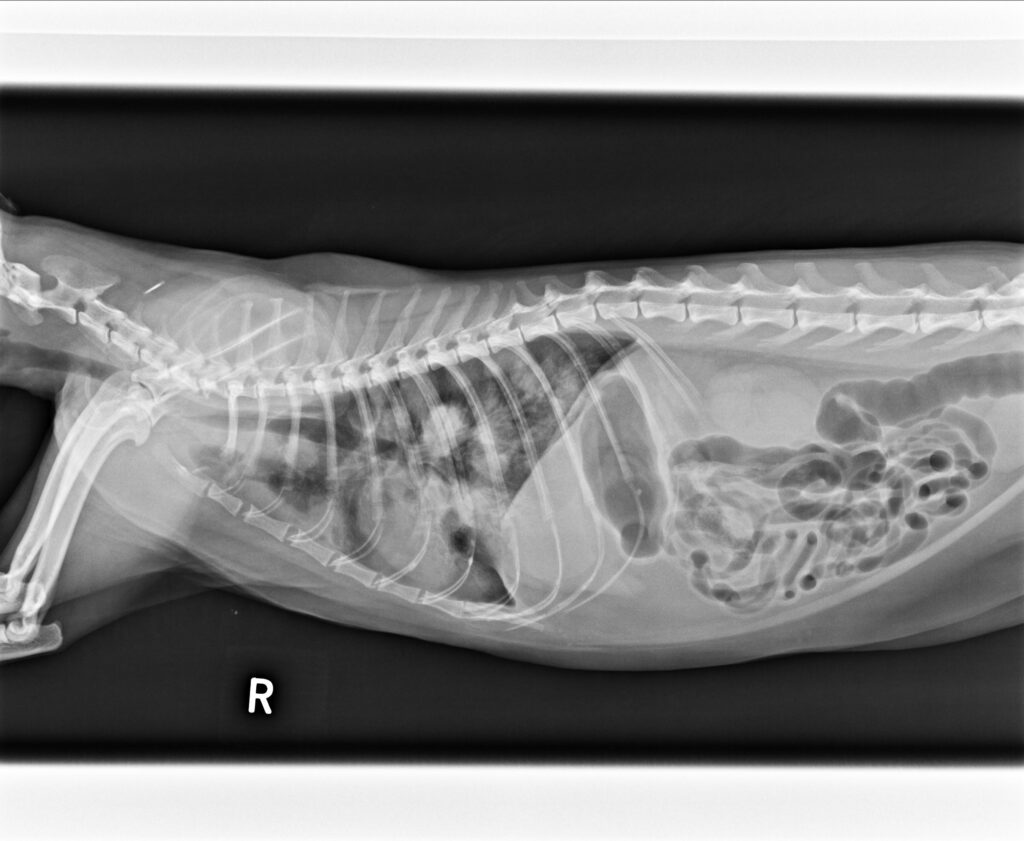

2023/5/11,一位街貓5.3公斤,3歲的橘貓因為很喘被附近的愛心人士帶來就診。愛心人士表示平時橘貓在他們家附近閒晃,他們就是定時餵食飼料,最近沒看到橘貓,再看到橘貓時就是一副很喘的樣子來找他們。愛心人士擔心之餘,經人介紹前來看診;在緊急為橘貓照完X光後,果然是罹患了肺炎。

胸腔X光1-3張見到瀰漫性結節團塊浸潤